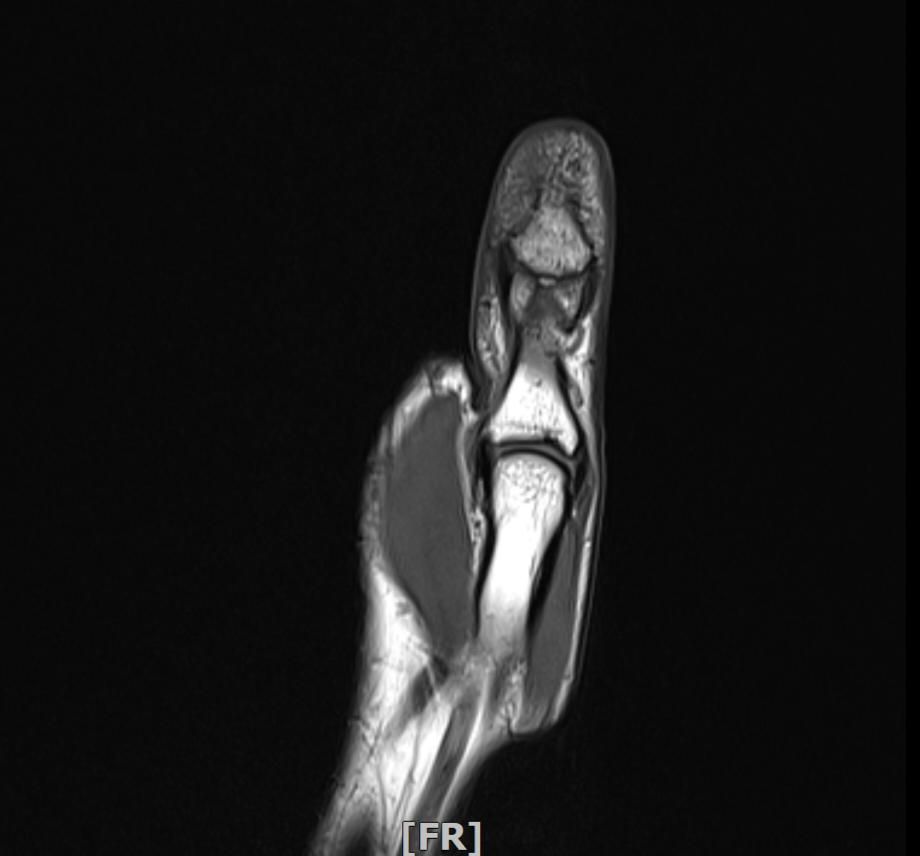

왼손 엄지손가락 부상 mri판독부탁드립니다

임팩에 장갑이 말리면서 엄지도 같이 말렸습니다

현재 손이 가끔 욱씬거리고 평소보다 뻣뻣하며 불안정감이 있는듯 합니다. mri사진으로 판독 가능하실까요 감사합니다.

• 4번 째 사진

정확한 판독을 하긴 어렵지만 연부조직의 주변부의 염증이 보여집니다.

올려주신 사진 상에서는 특별하게 큰 문제가 없을 수 있으나 부상과정에서 인대나 힘줄에 발생했던 부상으로 인해 긴장감이나 움직임 제한, 통증이 나티나는 경우에는 치료를 받아보시는 것도 좋겠습니다.

Mri 판독은 영상 전문의가 직접 이미지를 확인해야 정확하지만 엄지 부상 후 욱씬거림과 뻣뻣함, 불안정감은 인대 손상이나 골절, 건초염 가능성을 시사합니다. Mri에서는 인대 파열, 연골 손상, 골수 부종 등을 중점적으로 평가합니다. 증상이 지속되면 정형외과 전문의에게 영상 판독과 임상 진단을 반드시 받는 것이 안전합니다!